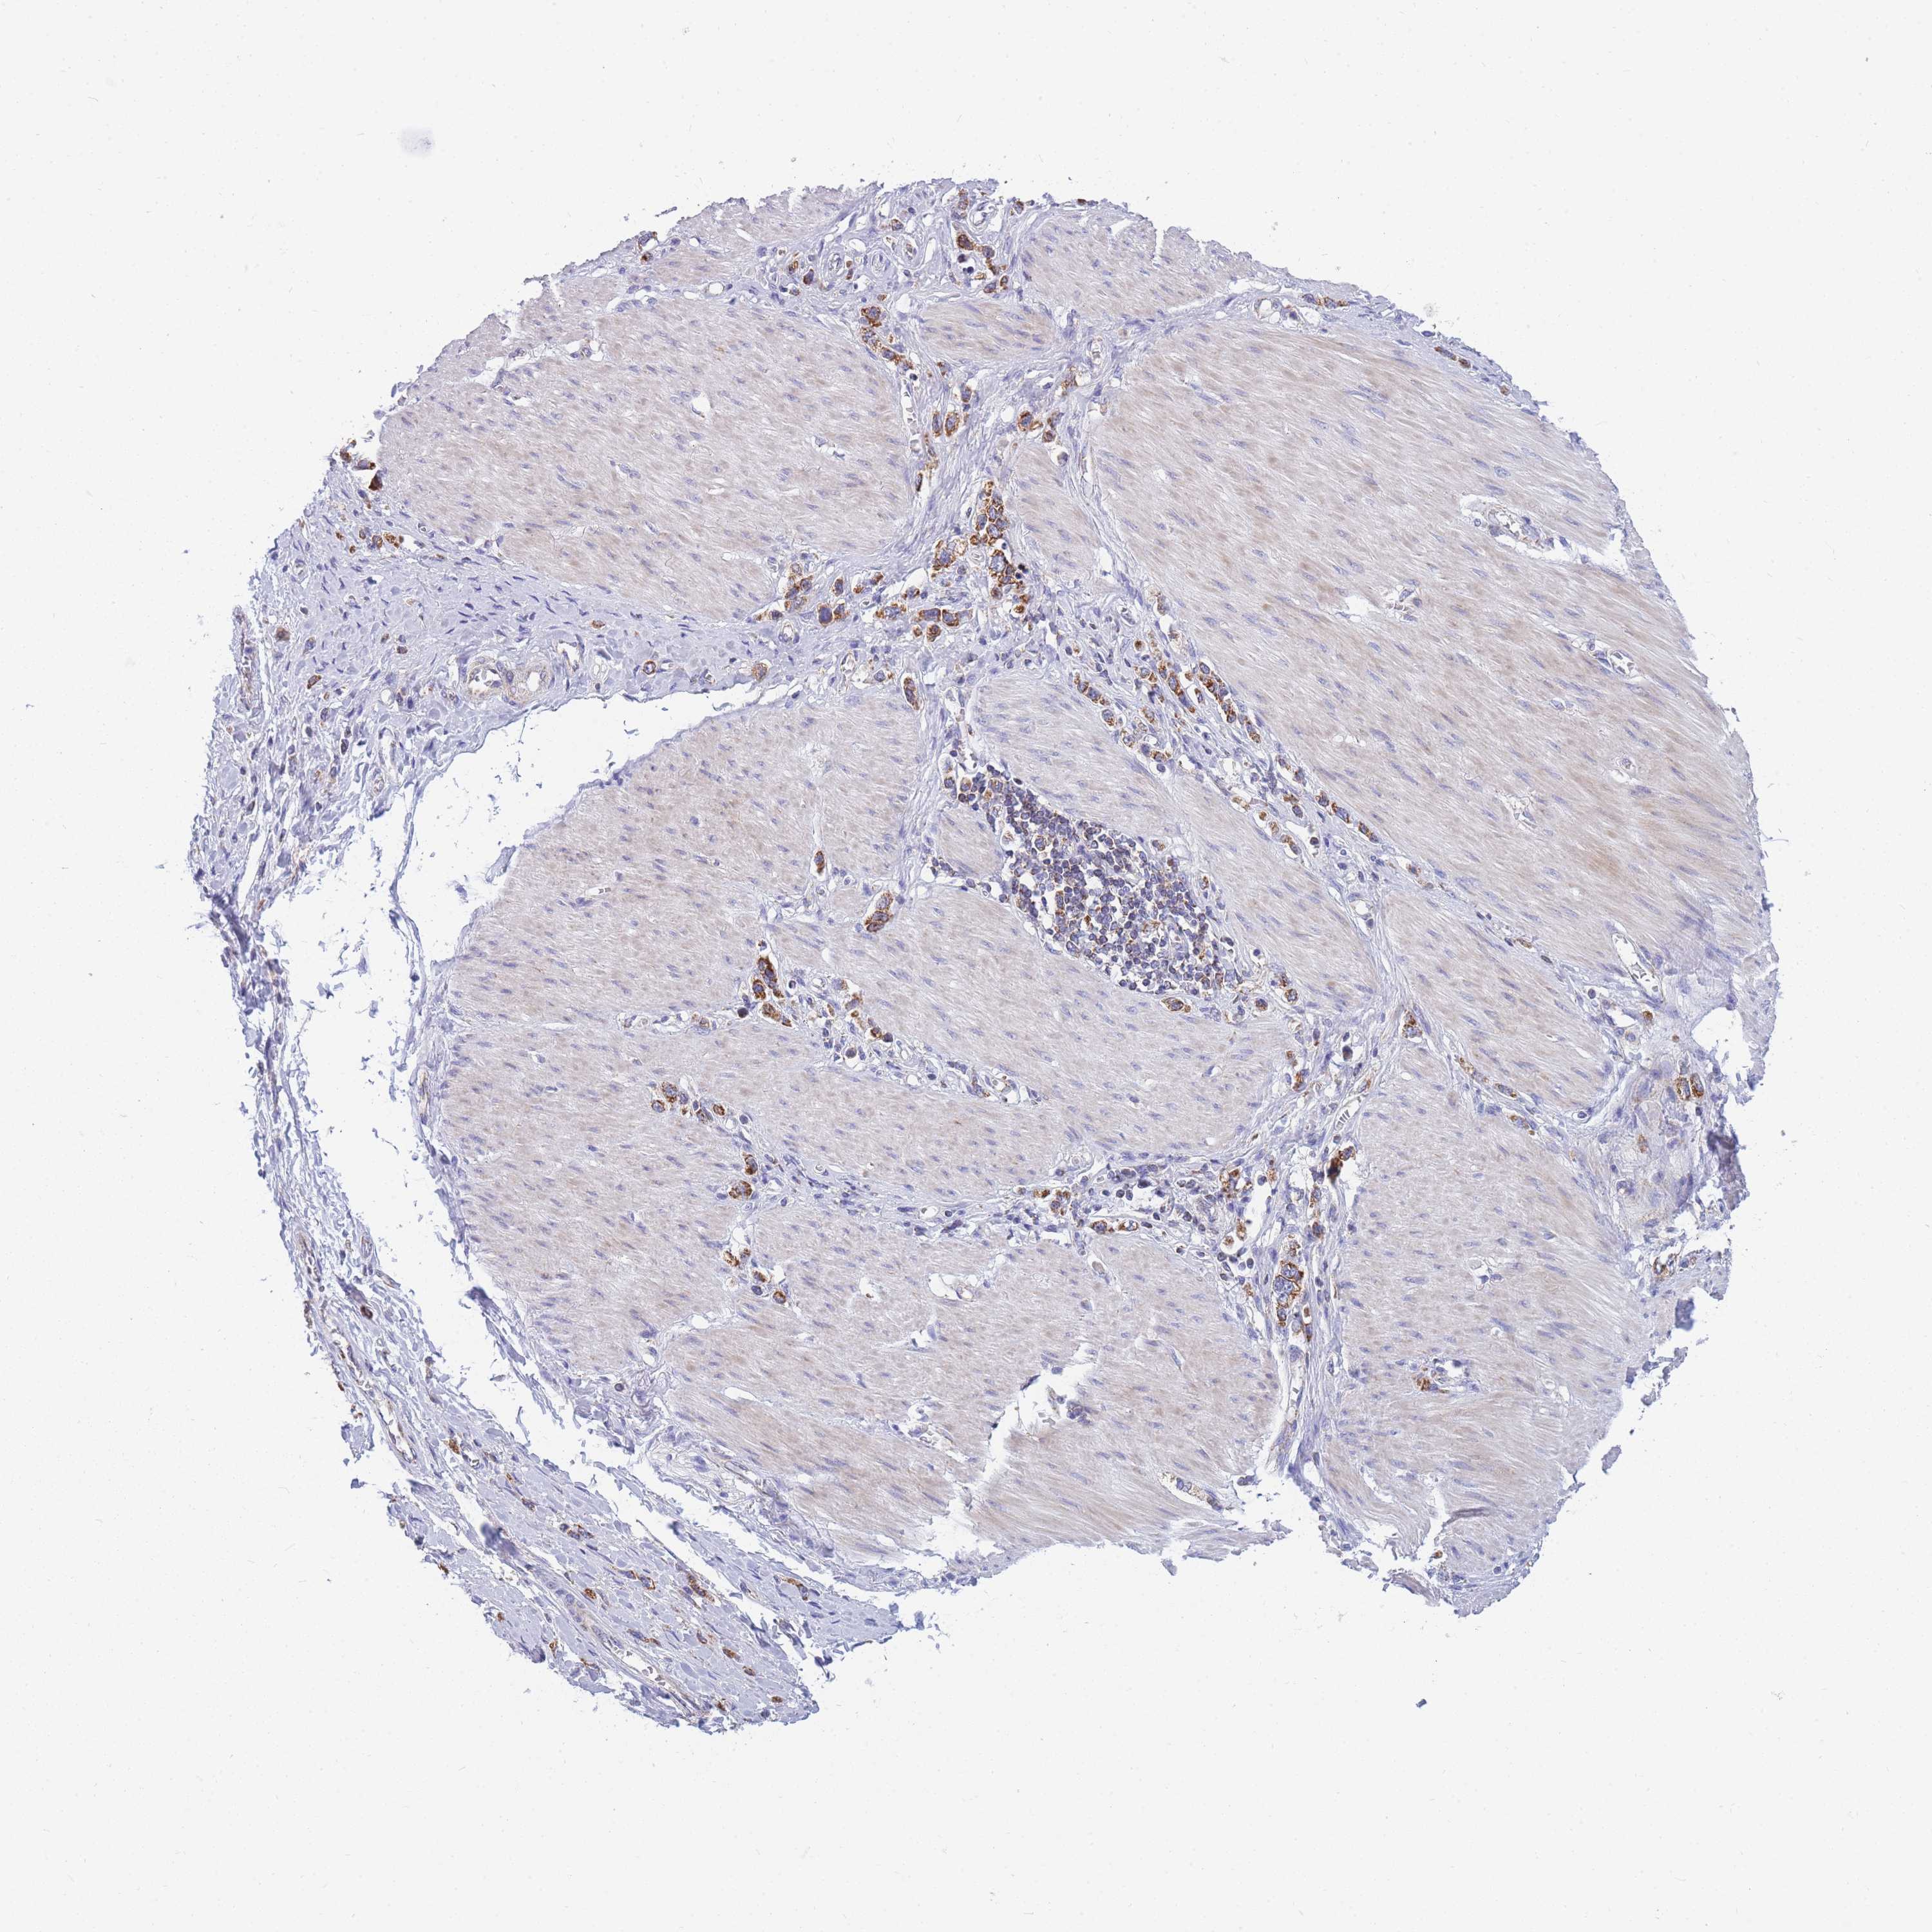

STOMACH CANCER - Protein expressioni

A mouse-over function shows sample information and annotation data. Click on an image to view it in a full screen mode. Samples can be filtered based on level of antibody staining by selecting one or several of the following categories: high, medium, low and not detected. The assay and annotation is described here.

Note that samples used for immunohistochemistry by the Human Protein Atlas do not correspond to samples in the TCGA dataset.

Antibody stainingi

Antibody staining in the annotated cell types in the current human tissue is reported as not detected, low, medium, or high, based on conventional immunohistochemistry profiling in selected tissues. This score is based on the combination of the staining intensity and fraction of stained cells.

Each image is clickable and will lead to virtual microscopy that enables deeper exploration of all samples and also displays staining intensity scores, fraction scores and subcellular localization as well as patient and tissue information for each sample.

Antibody HPA043752

Antibody HPA050345

Staining

High

Medium

Low

Not detected

Intensity

Strong

Moderate

Weak

Negative

Quantity

>75%

75%-25%

<25%

None

Location

Nuclear

Cytoplasmic/membranous

Cytoplasmic/membranous,nuclear

Adenocarcinoma, NOS